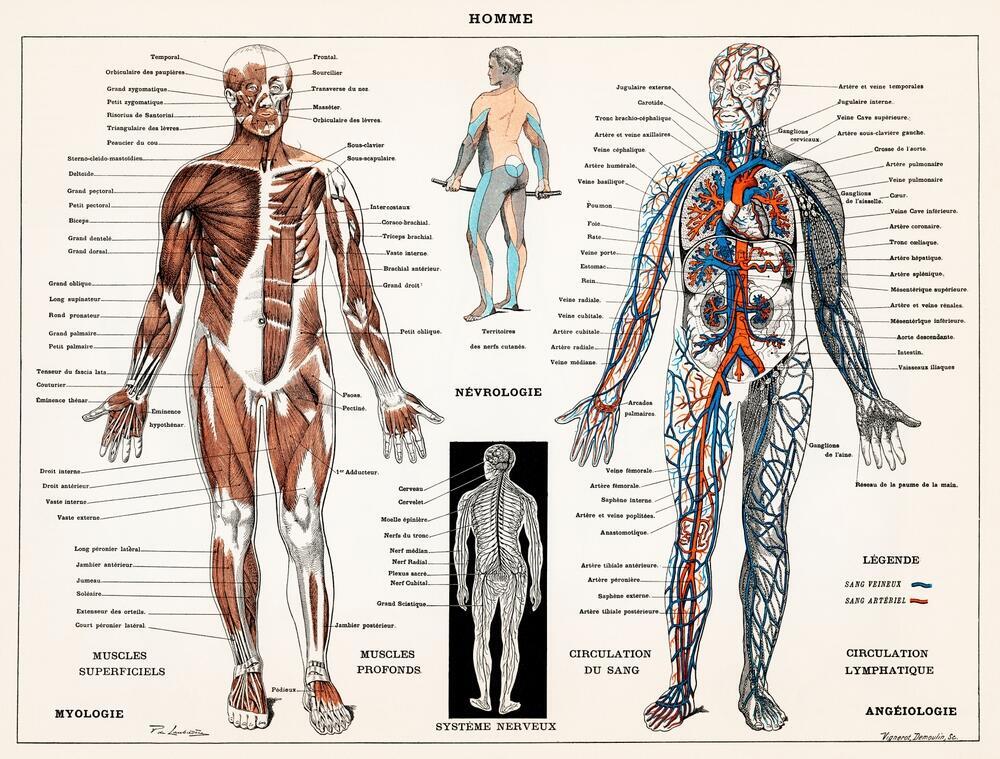

An old anatomical diagram. The experiment’s results challenged the anatomical assumptions of the time

(Photo: Shutterstock)

The findings, published in 1999 in the British Medical Journal, challenged a number of long-held medical assumptions. One central discovery overturned the centuries-old belief that the penis moves in and out of the vagina in a straight line, a depiction found in early anatomical illustrations, including a famous 1492 drawing by Leonardo da Vinci.

The MRI images showed a very different reality. During erection, the penis curves inside the woman’s body and adapts to her anatomy in a natural motion that does not cause pain. Researchers likened the shape to a boomerang. They also discovered that about one-third of the penis consists of a “root” that remains inside the body even when flaccid, a fact previously unknown to medicine.

Unexpected findings emerged regarding the female body as well. During sexual arousal without penetration, researchers observed the uterus shifting upward and the front wall of the vagina lengthening. Contrary to earlier theories, there was no increase in uterine volume. These observations contradicted classical anatomy textbooks and highlighted how much medical knowledge about female sexuality had long been based on assumptions rather than direct observation.